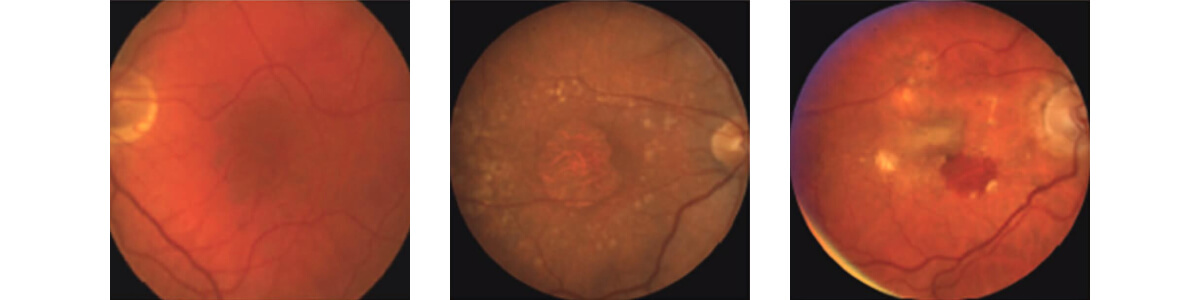

Left to right: Normal macula, Dry AMD with drusen, and central geographic atrophy, Wet AMD with bleeding and scar tissue

More than 90% of patients diagnosed with AMD have the dry form, which is often associated with a slower progression of the disease that occurs over many years. It is characterized by drusen formation (yellow deposits under the retina that are made up of lipids, a fatty protein), retinal degeneration, and a gradual wearing away of the retina called atrophy. If these areas of retinal degeneration group together into larger areas, it is called geographic atrophy which is a more advanced stage of the disease. Most patients with early dry AMD with mild retinal changes will have no or minimal problems with their vision. However, in its most advanced form, dry AMD can cause profound central vision loss, often with preserved peripheral (side) vision.

This form of AMD is characterized by the development of abnormal blood vessels known as choroidal neovascular membranes (CNVM) that disrupt the retina and cause leakage of fluid. This growth of abnormal blood vessels can result in vision loss due to fluid build-up in the retina (macular edema), bleeding in the retina, and scar tissue formation (fibrosis). Wet AMD is generally associated with more rapid visual loss over days to weeks compared to the slower progression of dry AMD.